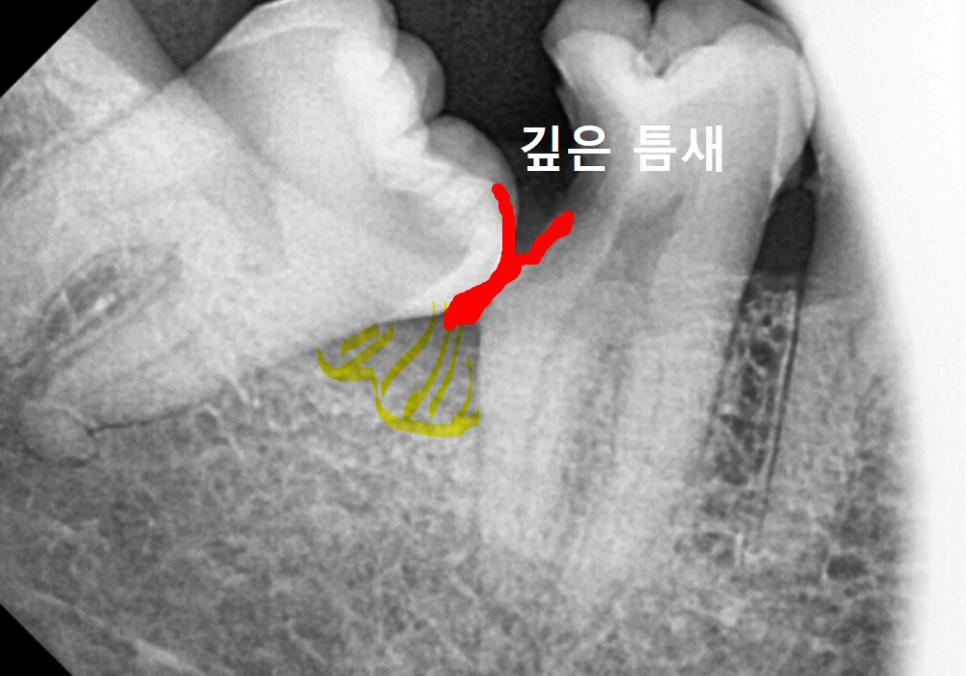

하지만 치아가 옆으로 누우면

앞 치아와 만나는 지점에 아주

깊고 좁은 틈새가 생깁니다.

250523

이 틈은 일반적인 칫솔질은 물론이고

치실이나 치간칫솔로도 닦기가 참 어려운

'사각지대'가 됩니다.

음식물이 자꾸 들어가 쌓이면서

세균이 번식하기 가장 좋은 환경이 되는 것이죠.

더 무서운 점은 충치가

사랑니에만 생기는 게 아니라,

멀쩡했던 앞쪽 어금니의 뒷벽을 타고

내려간다는 것입니다.

환자분 역시 이 틈새에서 시작된 충치가

앞 어금니 신경까지 깊숙이 침범해

치아가 약해졌고, 결국 딱딱한 음식을 씹을 때

버티지 못하고 깨져나간 것이었죠.

또한, 음식물 찌꺼기로 인한 만성 염증 때문에

치아를 지탱하는 뼈까지

야금야금 녹아내린 상태였습니다.